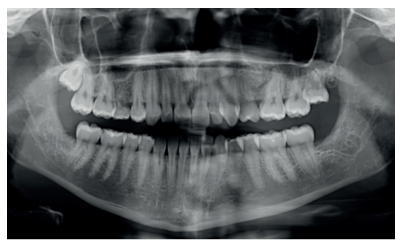

Caso clínico: se presenta un caso clínico de una mujer de 20 años, sin antecedentes médico-quirúrgicos de interés, que acudió a consulta remitida por su ortodoncista, para la extracción de un premolar maxilar retenido, en posición invertida. Tras la extracción del premolar y del tercer molar inferior retenidos, se obtuvo dentina procedente de ambos, para la regeneración ósea guiada del defecto resultante de la extracción del premolar, realizando revisiones a la semana y a los 4 meses de la intervención.

Clinical case: a clinical case of a 20-year-old woman is presented, with no interesting medical record, who went to dental clinic for removal of an inverse maxillary bicuspid retained. After maxillary bicuspid and lower third molar extractions, autogenous dentin was obtained from both teeth, to perform a guided bone regeneration of the bicuspid defect. A week and 4-month check-up were carried out.

El objetivo de este caso clínico es presentar la eficacia de la dentina autógena como material de injerto en un procedimiento de ROG, tras la exodoncia de un premolar superior izquierdo retenido, en posición invertida.